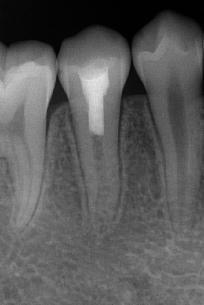

过牙髓再生治疗,促进牙髓坏死的年轻恒牙牙根进一步发育,牙髓活力测试呈阳性 。

术后3